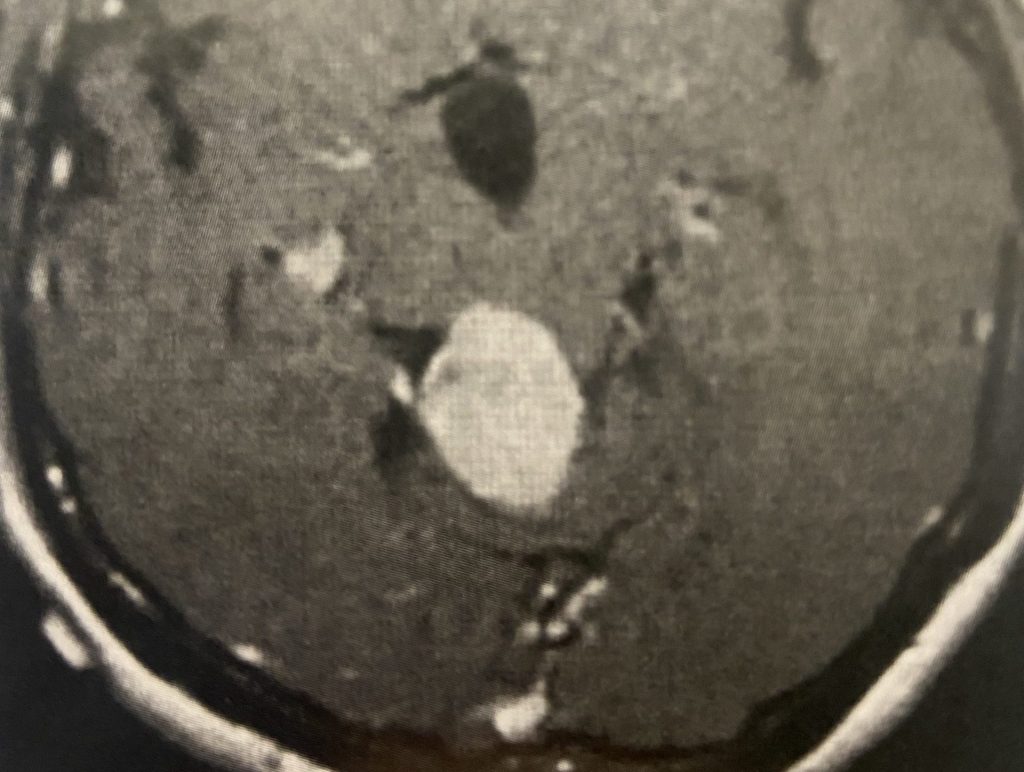

Subsequently, the hydrocephalus resolved and the patient did not require shunting. Her pre-operative symptoms all resolved. Follow up MRI demonstrated complete removal of the tumor.

Figure 4

Postoperative post contrast axial MRIs demonstrating complete removal of the tumor with resolution of the hydrocephalus.